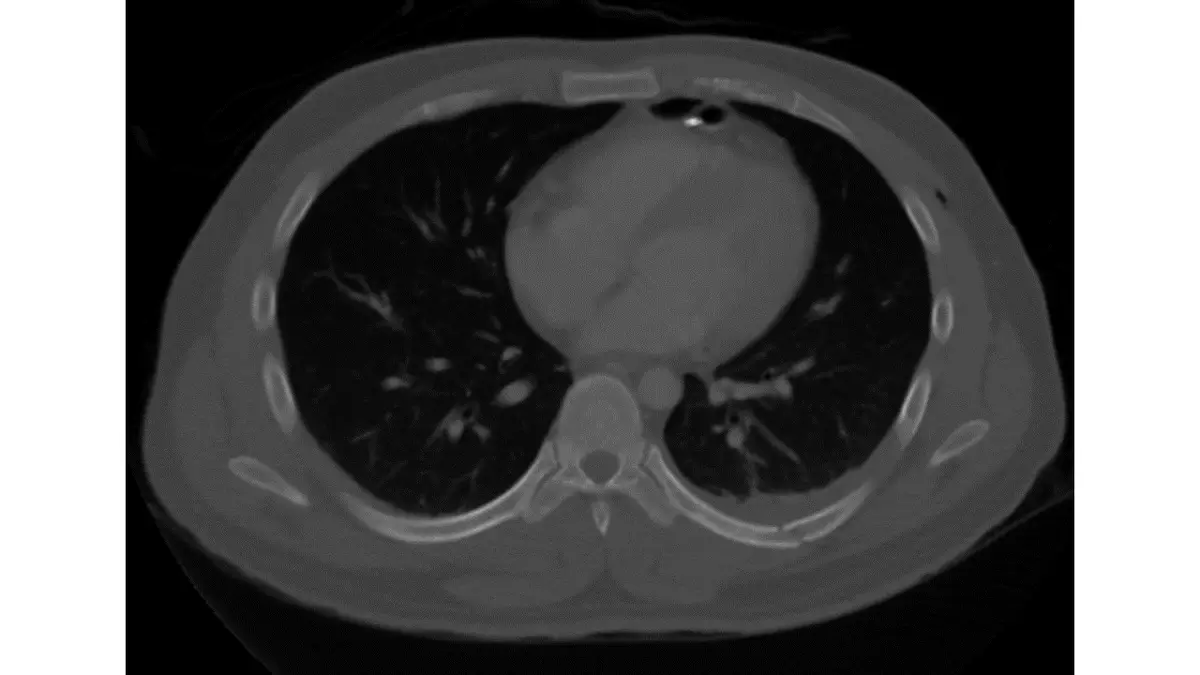

胸部電腦斷層攝影呈現如下圖,下列那一項最正確?

Amediastinal window

Blung window

Cbone window

Dpleural window

本圖為胸部 CT 軸位(axial)切面。觀察重點如下:

骨骼表現:肋骨和胸椎椎體呈亮白色,且骨皮質(cortex)與骨髓腔(medullary cavity)之間的皮髓質分界(corticomedullary junction)清晰可辨。骨骼細節(如皮質厚度、小梁骨紋理)得到優化顯示,這是骨骼窗的典型特徵。

肺野表現:兩側肺野呈深黑色。這是因為骨骼窗的窗位(window level, WL)設定偏高(約 +300 至 +400 HU),窗寬(window width, WW)極寬(約 1500–2000 HU),顯示範圍約為 至 HU。肺組織的 HU 值約在 至 HU,落在顯示範圍下緣或以下,因此呈黑色。

縱膈腔表現:心臟和大血管等縱膈腔軟組織結構呈灰白色,但細節分辨能力相對不如縱膈腔窗(mediastinal window)。

整體判讀:骨骼細節清楚、皮髓質分界明顯、肺野